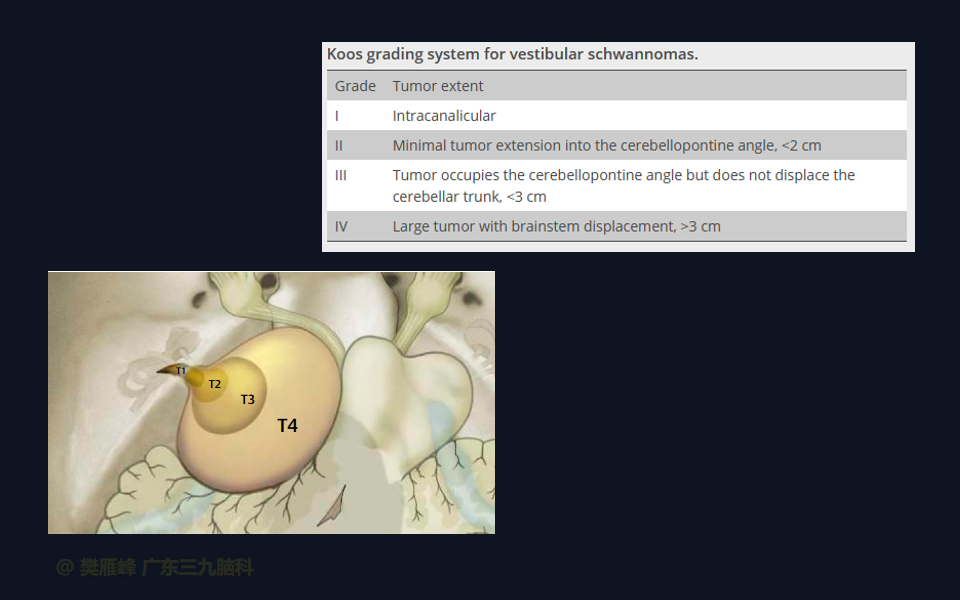

在这个二维手术视频中,展示了一种经枕下乙状窦后入路束膜下分离保留面神经的方法。患者是一名51岁的男性,有1年右耳听力下降伴耳鸣、无步态不平衡病史,术前有右侧轻度面瘫,神经影像学显示右侧桥小脑角区约30×30×29mm的囊实性占位,增强后实性部分及囊壁可见明显强化。他接受了经乙状窦后入路保留面神经的方法,术中肿瘤全切除,面神经被肿瘤挤压成薄膜状覆盖于三叉神经表面。术后面瘫加重,听力未能保留,神经影像学显示肿瘤全部切除。我们展示了安全的颅神经保护和肿瘤切除的细微差别和技术要点,以及手术技术。

在这段手术视频中,展示了一名51岁男性的病例,他因右耳听力下降伴耳鸣1年余发现的右侧听神经瘤。